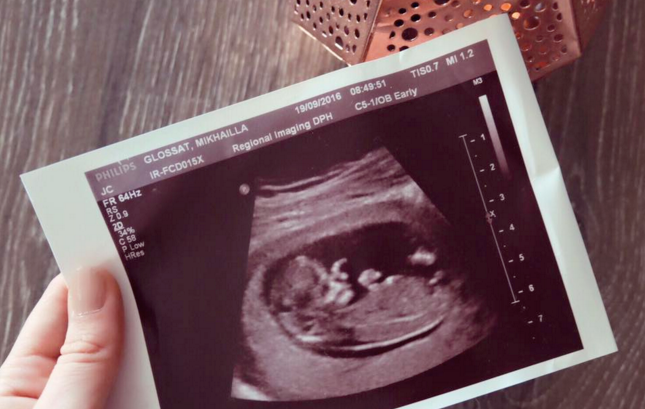

Week 12:

It came and it went, probably the most significant milestone to date as we had our big nuchal scan – the baby was showing low risk and was a happy healthy rolling baby that was waving it’s little hands and legs about. It was cute, and surreal that in 12 short weeks that little bean had become a baby we made. The heart rate measured at 152bpm. Feeling still unpredictably sick at times, and with cravings! I finally had cravings – and my god they are so random.